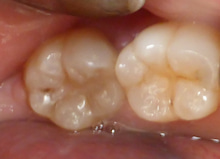

今日は 検診と歯石をとることを希望して来院された20代の方の紹介です。

ほとんど歯医者に行ったことがないらしく、

痛いところもないそうです。